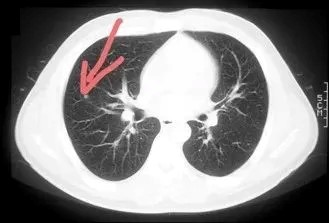

2、胸部肿瘤筛查

低剂量螺旋CT是当前公认的肺癌有效筛查手段,可检出早期、超早期的“毫米级”微小肺部肿瘤。

为了进一步降低对体检者的辐射风险,2015年,癌研有明医院体检中心引进了超低剂量CT,辐射剂量从1.54 mSv降为0.40 mSv;2016年经过调整拍摄条件,进一步将剂量降低到0.12 mSv,达到与X光片相似程度的辐射,但效果却远远优于X光片,同样能发现“毫米级”肺部肿瘤。